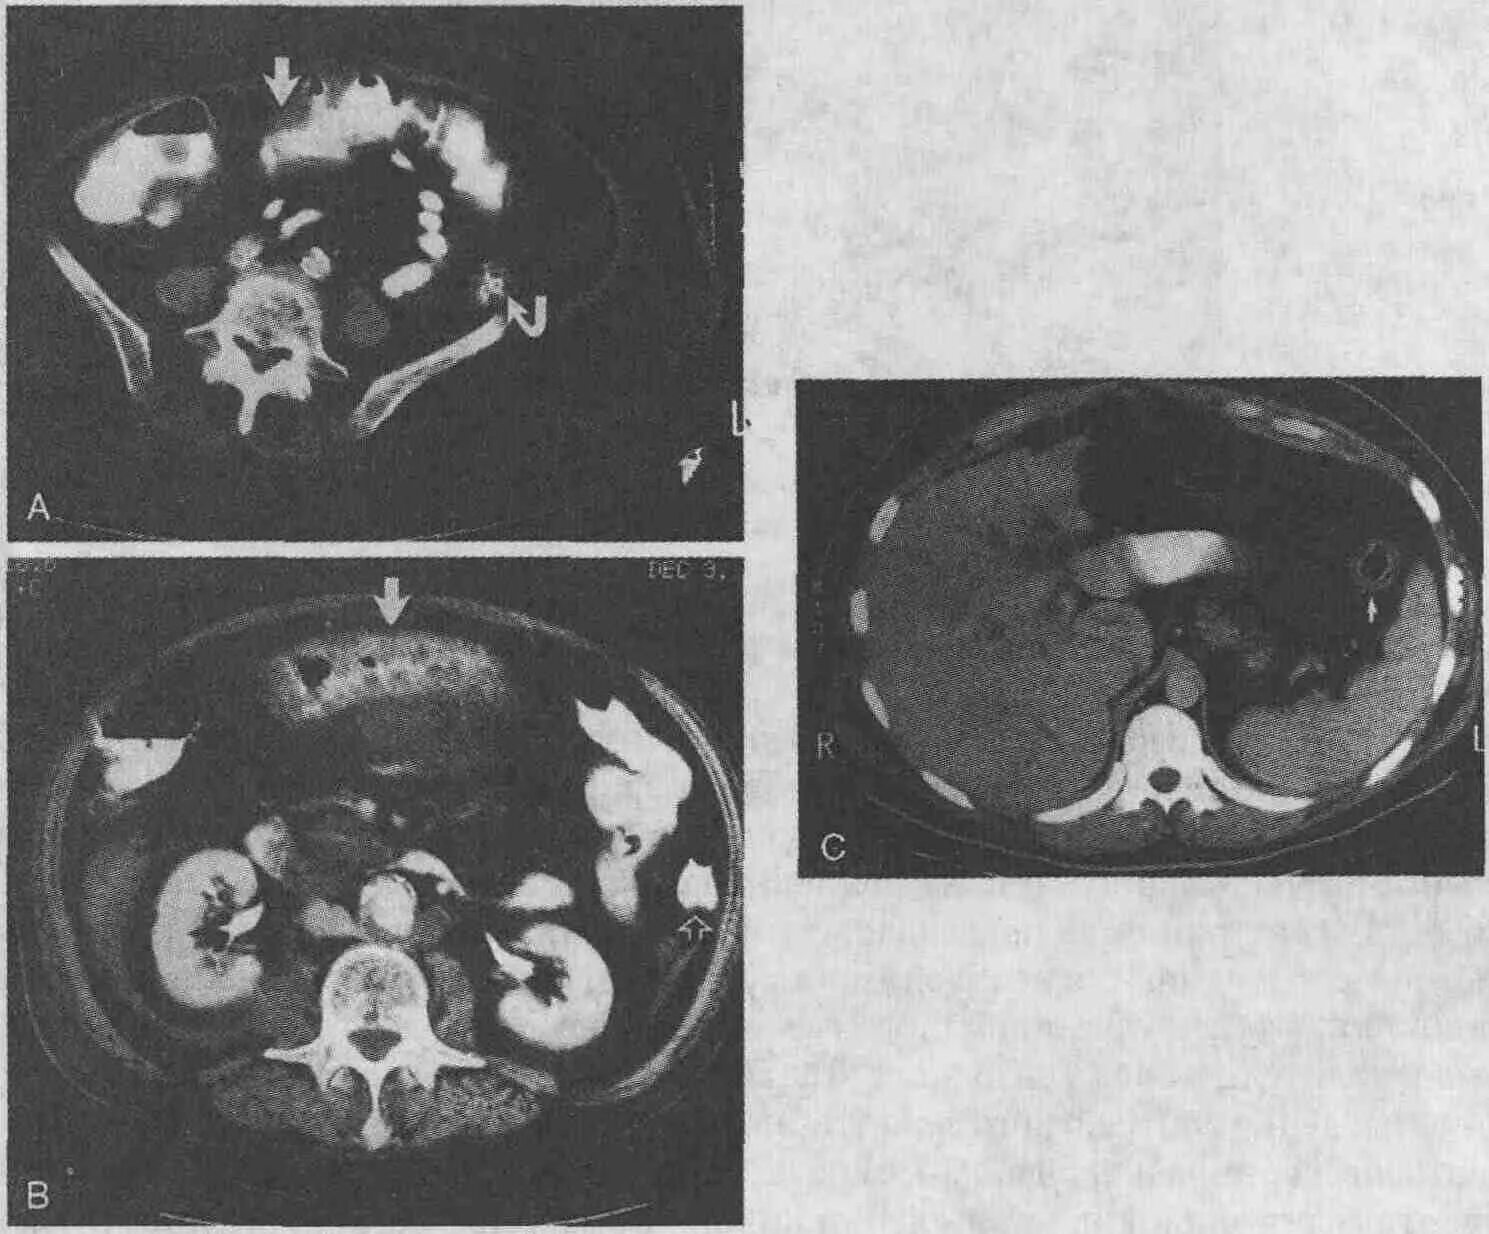

Рак прямой кт